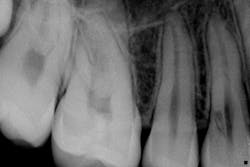

This actually has a huge bearing on dealing with resorption. External resorption versus internal resorption—when diagnosing, it makes all the difference. In my hands (and heart), I believe the only type that stands any chance whatsoever of treatment success is internal resorption. And even then, it depends on the extent of the damage.

When evaluating and discussing external resorption, I commonly tell my patients, “I cannot make your bones and gingiva stop eating the tooth. I do not have that power.” As we have all seen, external resorption can occur in various places and teeth. However, it almost always seems to be around the area of the alveolar crest, which, in my opinion, makes restoring it almost impossible. At least with internal resorption, one has a chance. You must be aggressive in cleaning the canal way beyond the typical endo and particularly in the areas of the defect. That, my friends, is where the microscope comes in very handy.

Unless it is caught on the early end, it does not matter. Once the resorptive damage has extended beyond a certain point, the prognosis drops precipitously, regardless of whether it started internally or externally. If communication of the defect occurs from internal to external or vice versa, I find that the prognosis goes from questionable to hopeless.